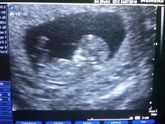

Ну что, была сегодня на втором скрининге. У меня будет Дочка!!! Узист пошутила, сказала, если я ошибаюсь, отрубите мне руку!!! Ничего не выросло. Девочка моя сегодня все показала, не стеснялась, чтобы мама уже убедилась, что можно выбирать для нее имя, … Читать далее